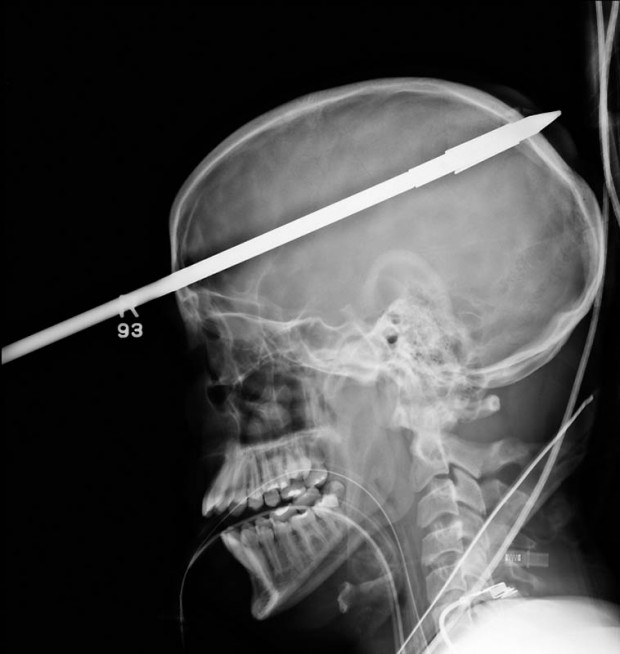

11. Копье от гарпуна, попавшее в голову 16-летнему мальчику на рыбалке.